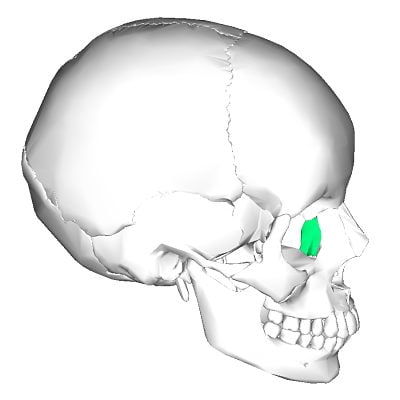

- El hueso lagrimal o unguis, es un hueso par, situado en la cara medial de cada cavidad orbitaria, ubicado entre el frontal, el etmoides y el maxilar.

- Es una lámina ósea, delgada e irregular.

- Para su estudio se describen dos caras y cuatro bordes.